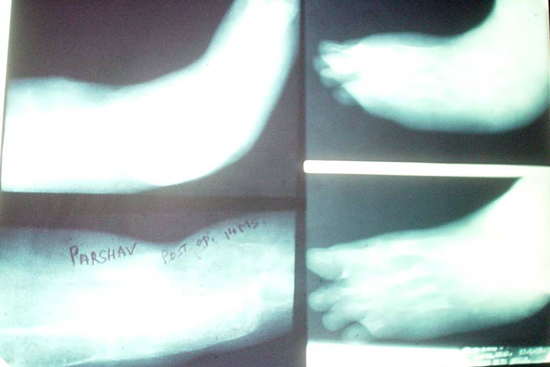

Limb Lengthening